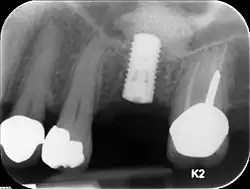

Unterkiefer

Im Unterkiefer ist die Höhe des Kieferknochens nach kaudal durch den Nervus mandibularis begrenzt. Dieser darf nicht tangiert werden, weil es sonst zu bleibenden Sensibilitätsausfällen insbesondere im Bereich der Unterlippe und des Kinns kommen kann. Die Mindestlänge eines Implantats beträgt 8 mm, wobei Implantatlängen von 10 bis 12 mm angestrebt werden. Reicht diese Höhe nicht aus, muss ein Knochenaufbau durchgeführt werden. Ähnliches gilt für einen nicht ausreichend breiten Kieferkammknochen, in den das Implantat eingebracht werden soll.

Im Oberkiefer erfolgt der Kieferaufbau analog dem des Unterkiefers mit Ausnahme des Bereichs der Oberkieferbackenzähne. Im Bereich der Zähne 15 – 17, bzw. 25 – 27 sind die Zahnfächer der Zähne (in der Regel) nur durch eine dünne Knochenlamelle, den Kieferhöhlenboden von der Kieferhöhle getrennt. Im Seitenzahnbereich des Oberkiefers erfolgt der Knochenabbau oft durch ein Absinken des Kieferhöhlenbodens bei weitgehend unveränderter äußerer Form des Alveolarkamms. Die Dicke des Kieferhöhlenbodens kann dabei bis zur Papierdicke reduziert werden. Um auch hier Implantate mit der entsprechenden Mindestlänge einbringen zu können, muss ein Knochenaufbau durchgeführt werden. Dieser erfolgt in der Regel durch einen Sinuslift.